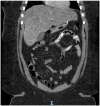

A Unique Presentation of COVID-19 in a Patient Post Sleeve Gastrectomy